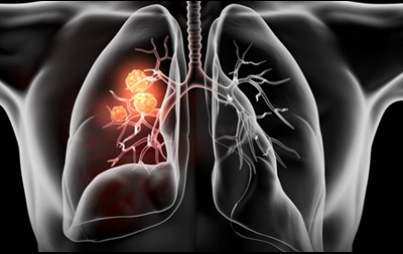

이번 기사에서는 폐암 초기 증상에 대해 자세히 정리해 알려 드리겠습니다 . 폐암은 국내암 사망률 1 위로, 과거에는 흡연이 폐암의 주된 원인 이었지만 , 현재는 비흡연 폐암 환자도 대폭 증가했습니다 . 폐암은 의학 기술로 발달하여 생존율이 높아지고 있습니다 . 폐암의 초기 증상은 무엇인가를 알아보겠습니다.

폐암의 초기 증상